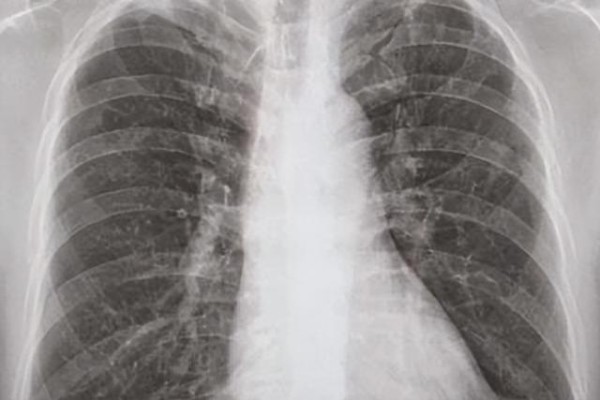

67岁的陈大爷,一直觉得自己身体底子好,不爱上医院。只是这段时间,他总是夜里咳嗽、出虚汗,白天没精神,还开始消瘦。家里人劝了好几次,他才勉强去社区医院拍了个胸片。

结果出来,医生脸色严肃——疑似肺结核,需要转诊进一步确诊治疗。